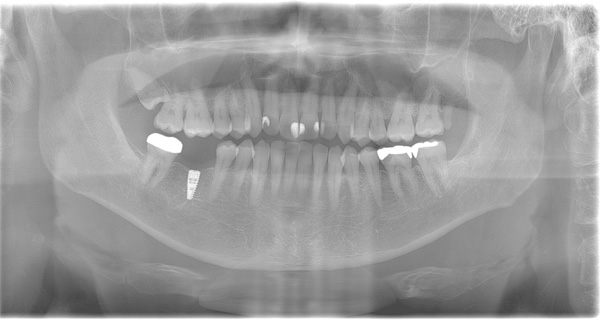

BEFORE

| 年代・性別 | 50代 女性 |

|---|---|

| 主訴 | 左上のブリッジがグラグラして外れそう |

| 治療期間 | 約18ヶ月 |

| 費用 | 1,600,000円 |

| 治療内容 | インプラント、骨造成、サイナスリフト、セラミック修復 |

| 治療に伴うリスク | インプラント周囲炎 セラミックの破折、脱離 |